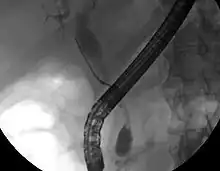

Bien que l'imagerie non invasive abdominale puisse se révéler utile dans l'établissement du diagnostic, l'imagerie locale des voies biliaires s'avère souvent nécessaire. La cholangio-pancréatographie rétrograde par voie endoscopique (CPRE, ou en anglais ERCP — ou cathétérisme endoscopique bilio-pancréatique) est une procédure combinant l'endoscopie et la fluoroscopie réalisée par un gastro-entérologue ou un chirurgien, largement utilisée dans ce but.

Bien qu'invasive et présentant des risques per- et post-opératoires (développement de pancréatite dans 5 % des cas, risques classiques inhérents à l'endoscopie), elle présente l'avantage de permettre un brossage pour examen cytologique, d'obtenir une biopsie et de placer un stent ou de procéder à d'autres interventions pour éliminer l'obstruction biliaire (dilatation des voies biliaires ou lyse d'une éventuelle lithiase)[10]. Une échographie endoscopique peut aussi être réalisée en même temps[60]. L'IRM au niveau pancréatique et biliaire est une alternative non-invasive à l'ERCP[61],[62],[63]. Certains auteurs ont suggéré que l'IRM pourrait supplanter l'ERCP dans le diagnostic des cancers biliaires[64],[65],[66],[67].

- Image d'une cholangiopancréatographie IRM d'un cholangiocarcinome